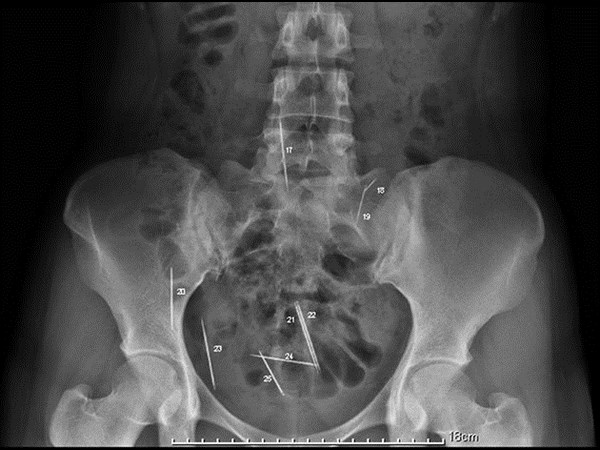

மருத்துவ உலகம் கண்டு வியந்த எக்ஸ் ரே படங்கள்

வயிற்றில் கத்திரிகோல் உள்ளது.